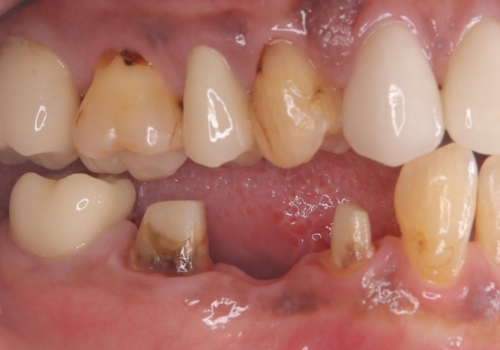

コアごと脱離して来院し、フェルールの獲得が厳しいためコアが立てられないので抜歯することになりました。

インプラントとブリッジの治療を提案し早く噛めるようにしてほしいという要望があったためブリッジにて治療をすることになりました。